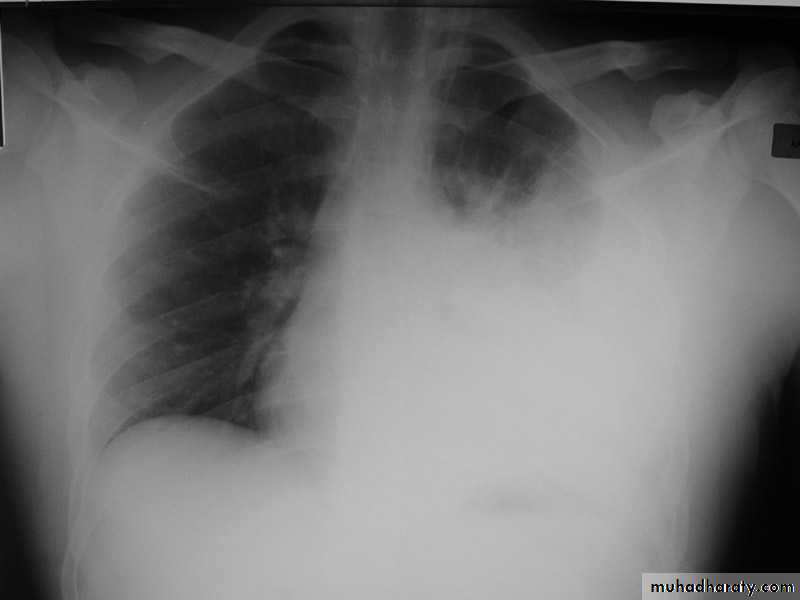

Pleural effusionX-ray of pleural effusion

Massive right effusion